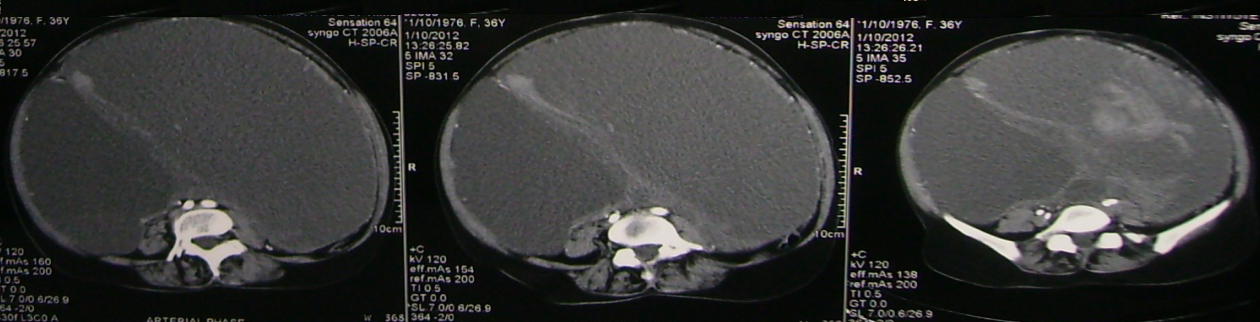

Stage 4: distant metastases, pleural effusion, pleural nodules or focal thickening suggest this stage. Accuracy for detecting peritoneal deposits is dependent on their location, size and presence of ascites. MRI and CT have similar sensitivity in detection of peritoneal deposits greater than 1cm. Peritoneal deposits appear has rounded, cake like, stellate or ill-defined masses. However deposits in mesentery/ implant on surface of bowel and calcified deposits are better seen in CT. Adjacent pelvic organ involvement may be difficult to diagnose accurately. In large ovarian tumour, it may be difficult to identify uterus which is partially or completely surrounded by tumour. Pelvic side wall invasion is suspected when tumour lies within 3mm of pelvic side wall or when iliac vessel are surrounded or displaced by tumour. Focal obliteration of fat plane or tumour encasement of bladder or recto sigmoid is highly suspicious of involvement of the structures. Staging accuracy is 80-90% (Figures 9 & 10).

Figure 9: Carcinoma of ovary stage 4 disease pleural effusion.

Figure 10: Omental caking with carcinoma of the ovary.